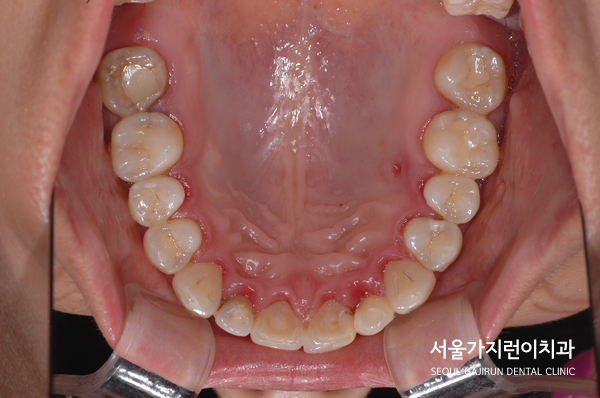

환자분의 경우에는 대구치가 손실된 것을 사진처럼 볼 수 있었는데요. 네 곳의 발치 공간을 임플란트 없이 닫는 것을 희망하고 계셨습니다. 여기에 입을 다물었을 때 아랫입술이 나와보이는 주걱턱 성향을 갖고 있어 앞니가 거꾸로 물리는 듯한 모습도 발견할 수 있었는데요.

그래서 본원에서는 환자의 상태를 확인한 후에 사랑니를 어금니도 대체하는 치아교정을 진행했었는데요. 환자분께는 레버암과 미니스크류를 동시에 사용해 어금니가 쓰러지지 않고 전방으로 이동하면서 사랑니를 끌어다 사용할 수 있도록 치아교정 계획을 수립했었습니다.

결국 환자분이 원하는 것처럼 설측교정방식을 이용한 치아교정을 진행했으며 공간의 폐쇄와 더불어 사랑니를 세워 어금니로 활용할 수 있게 만들었는데요. 교정을 마친 후를 보면 정상교합으로 달성된 것을 확인할 수 있으며 발치로 인한 공간을 잘 폐쇄하였습니다. 여기에 주걱턱 느낌도 교정을 마쳤는데요. 모든 케이스에 적용가능한 것은 아니지만 상기 환자와 비슷한 사랑니 치아교정이 고민된다면 교정전문치과 서울가지런이치과 교정과 의원을 방문해보시기 바랍니다.